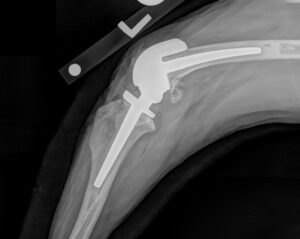

At Fitzbionics, we developed a rotating hinge total knee replacement which restores knee function even when all of the ligaments are damaged. 3D-printed guides allow the removal of the bottom of the femur and the top of the tibia. The marrow cavities were filled with cement which immediately fixed stems of both femoral and tibial implants, into which bone grew over time.  A unique hinge mechanism mounted on an axle and a spigot allowed both of his knees to flex, extend and rotate, whilst avoiding dislocation.